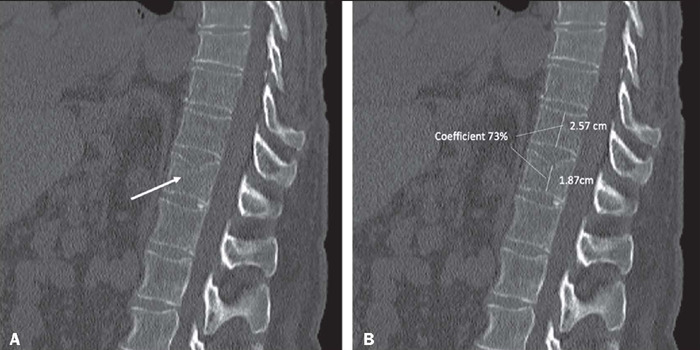

Objective: To describe the accuracy of HealthVCF, a software product that uses artificial intelligence, in the detection of incidental moderate-to-severe vertebral compression fractures (VCFs) on chest and abdominal computed tomography scans.

Materials and methods: We included a consecutive sample of 899 chest and abdominal computed tomography scans of patients 51-99 years of age. Scans were retrospectively evaluated by the software and by two specialists in musculoskeletal imaging for the presence of VCFs with vertebral body height loss > 25%. We compared the software analysis with that of a general radiologist, using the evaluation of the two specialists as the reference.

Results: The software showed a diagnostic accuracy of 89.6% (95% CI: 87.4-91.5%) for moderate-to-severe VCFs, with a sensitivity of 73.8%, a specificity of 92.7%, and a negative predictive value of 94.8%. Among the 145 positive scans detected by the software, the general radiologist failed to report the fractures in 62 (42.8%), and the algorithm detected additional fractures in 38 of those scans.

Conclusion: The software has good accuracy for the detection of moderate-to-severe VCFs, with high specificity, and can increase the opportunistic detection rate of VCFs by radiologists who do not specialize in musculoskeletal imaging.